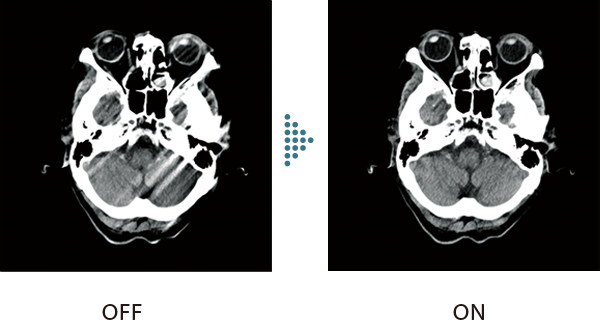

頭部CT検査で画像のブレを抑える

頭部撮影において、検査中の体動によるアーチファクトを補正します。